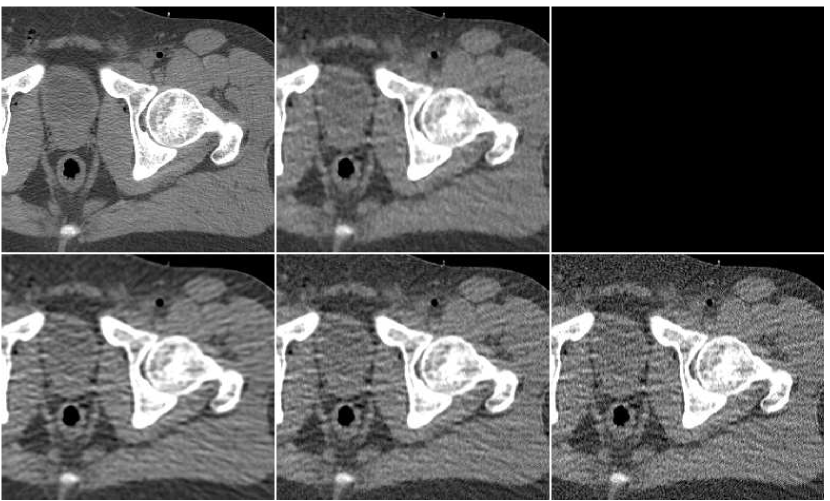

As a last experiment, we consider the special case where the ANN only performs a local filtering of the single version of the image, without a reference to the other versions. A neighborhood of radius ( pixels) was extracted for each location in the PWLS image, corresponding to iteration number . The fusion result is visually compared in Figure 14 versus the image produced from PWLS versions, as before. It can be observed that the processing by ANN reduces the noise appearing in the PWLS image, but it is slightly inferior to the fusion image produced from several PWLS versions.